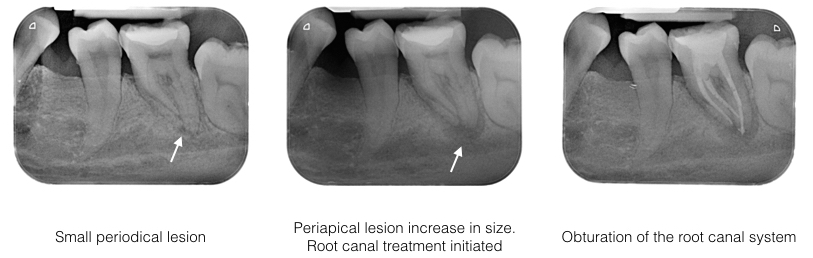

History: This British lady first noted pain while she was back for holiday in UK. The attending dentist advised her for a root canal treatment. When she return to Malaysia, her symptoms more or less resolve.

Examination: Tooth 36 has a large restoration. The tooth is mildly tender to percussion and not resposive to cold test. Radiograph showed the tooth with a small periapical lesion. Since the tooth does not cause much trouble at the time of examination, patient requested, to observe the condition further.

6 months later, the pain on the lower left 1st molar returns and the radiograpgh showed the periapical lesion has increased in size. Tooth was very tender to touch.

Diagnosis: Acute apical periodontitis of tooth 36

Treatment: Root canal treatment was carried out on tooth 36 under rubber dam isolation. Both mesial canals are curve. All 3 canals were cleaned and shaped. Calcium hydroxide dressing were placed for disinfection. One week review showed tooth 36 is no longer painful. Obturation was carried out on all the 3 canals.

RCT Case 2